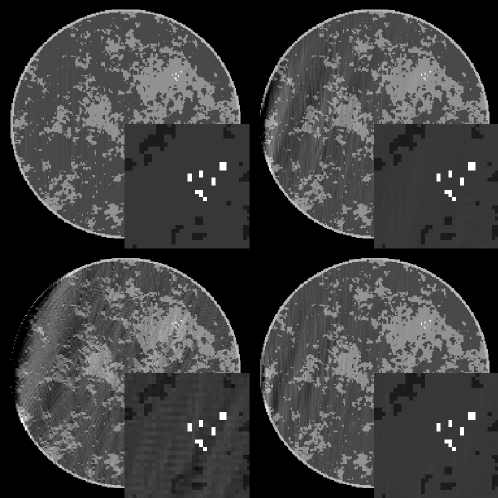

We demonstrate the application of the various accelerated CP algorithm instances on simulated CT data generated from the breast phantom shown in Fig. 3. The phantom, described in Ref. joergensen2011toward ; reiser2010task , is digitized on a 256 256 pixel array. Four tissue types are modeled: the background fat tissue is taken as the reference material and assigned a value of 1.0, the modeled fibro-glandular tissue takes a value of 1.1, the outer skin layer is set to 1.15, and the micro-calcifications are assigned values in the range [1.8,2.3]. The simulated CT configuration is described at the beginning of Sec. II.

The results of each algorithm are shown in Fig. 4. As the data are ideal, each algorithm drives the data-error to zero. The linear CG algorithm shows the smallest data RMSE, but we note similar slopes on the log-log plot of CG and CP2-EC during most of the computed iterations except near the end, where the slope of the CG curve steepens. The ART algorithm reveals a convergence slightly faster than CP2-EC, initially, but it is overtaken by CP2-EC near iteration 1000. We also note the impact of the algorithm acceleration afforded by the proposed convex feasibility framework in the comparison of CP2-EC and CP1-EC.

Because is designed to be left-invertible, we know also that the image estimates must converge to the breast phantom for each of the four algorithms. A similar ordering of the convergence rates is observed in the image RMSE plot, but we note that the values of the image RMSE are all much larger than corresponding values in the data RMSE plots. This stems from the poor conditioning of , and this point is emphasized in examining the shown image estimates at iteration 10000 for each algorithm.

While the image RMSE gives a summary metric on the accuracy of the image reconstruction, the displayed images yield more detailed information on the image error incurred by truncating the algorithm iteration. The CP2-EC, CP1-EC, and ART images show wavy artifacts on the left side; the limited-angle scanning arc is over the right-side of the object. But the CG image shows visually accurate image reconstruction at the given gray scale window setting.

The results of CP2-IC and CP1-IC are shown in Fig. 8. The data RMSE is seen to converge to the value established by the choice of . In the displayed images, there is a clear difference due to the choice of prior image. The image resulting from the zero prior shows a substantial drift of the gray level on the left side of the image. Application of a prior image consisting of constant background values over the object’s true support removes this artifact almost completely. These results indicate that use of prior knowledge, when available, can have a large impact on image quality particularly for an ill-conditioned system matrix such as what arises in limited angular-range CT.

In our first example with this two-set convex feasibility problem, we maintain the tight data-error constraint (a data RMSE of 0.002) but attempt to find an image with lower TV by selecting . The results for these constraint set settings, labeled “set 1”, are shown in Fig. 10. Interestingly, this set of constraints appears to be just barely infeasible; the CP2-ICTV result converges to an image TV of 4000.012 and a data RMSE of 0.00202. Furthermore, the dual variable magnitude increases steadily, an indication of an infeasible problem. The curves for image TV and data RMSE indicate convergence to the above-mentioned values, but we do not make theoretical claims for convergence of the CP algorithms with inconsistent convex feasibility problems.

In the second example, we loosen the data-error constraint to (a data RMSE of 0.0025) and seek an image with lower TV, , and the results are also shown in Fig. 10. In this case, the constraint values are met by CP2-ICTV, and the resulting image has noticeably less noise than the images with no TV constraint imposed shown in Fig. 8 particularly in the ROI containing the model micro-calcifications. The image RMSE for this constraint set in ICTV is 0.029, while the comparable image RMSE from the previous convex feasibility problem, IC, with no TV constraint shown in Fig. 8 is 0.037. Thus we note a drop in image RMSE in adding the image TV constraint, but a true image quality comparison would require parameter sweeps in for IC, and and for ICTV.